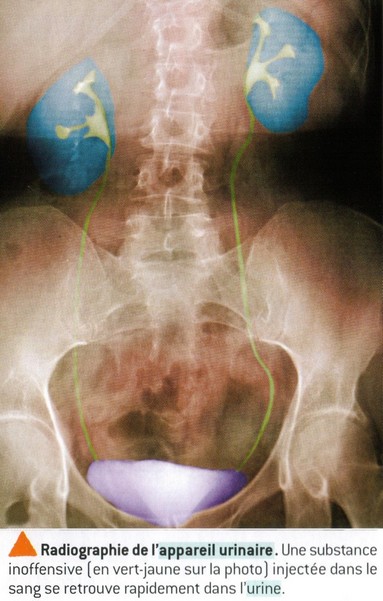

ORIGINE DE l'URINE